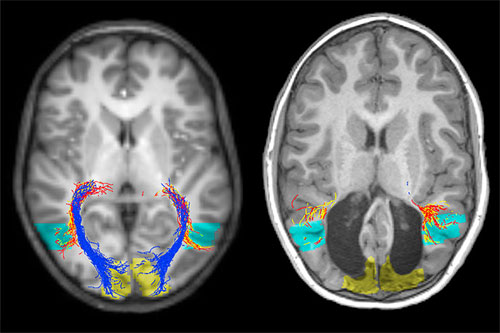

Când avea doar două săptămâni, băiatul a suferit o deteriorare gravă a cortexului vizual – parte a creierului care gestionează impulsurile senzoriale nervoase provenite de la nivelul ochilor – ca urmare a unei tulburări metabolice rare numite deficit de acil-Co-A dehidrogenază cu lanț mediu. Această condiție împiedică țesuturile să transforme anumite tipuri de grăsimi în energie.

Băiatul, denumit doar „B.I.” de cercetătorii de la Institutul de Medicină Regenerativă de la Universitatea Monash care au adus cazul în atenția comunității medicale, a ajuns să vadă fără cortexul său vizual, deși, de obicei, o situație ca aceasta ar duce la orbire corticală, o boală în care creierul obține în continuare informații senzoriale vizuale, dar nu poate procesa ceea ce este perceput, făcând ca persoana să simtă că are vedere, dar nu să și poată vedea. Băiatul, totuși, poate vedea aproape la fel ca orice alt copil de vârsta sa, este capabil să joace fotbal cu ceilalți colegi sau jocuri video și chiar să citească.